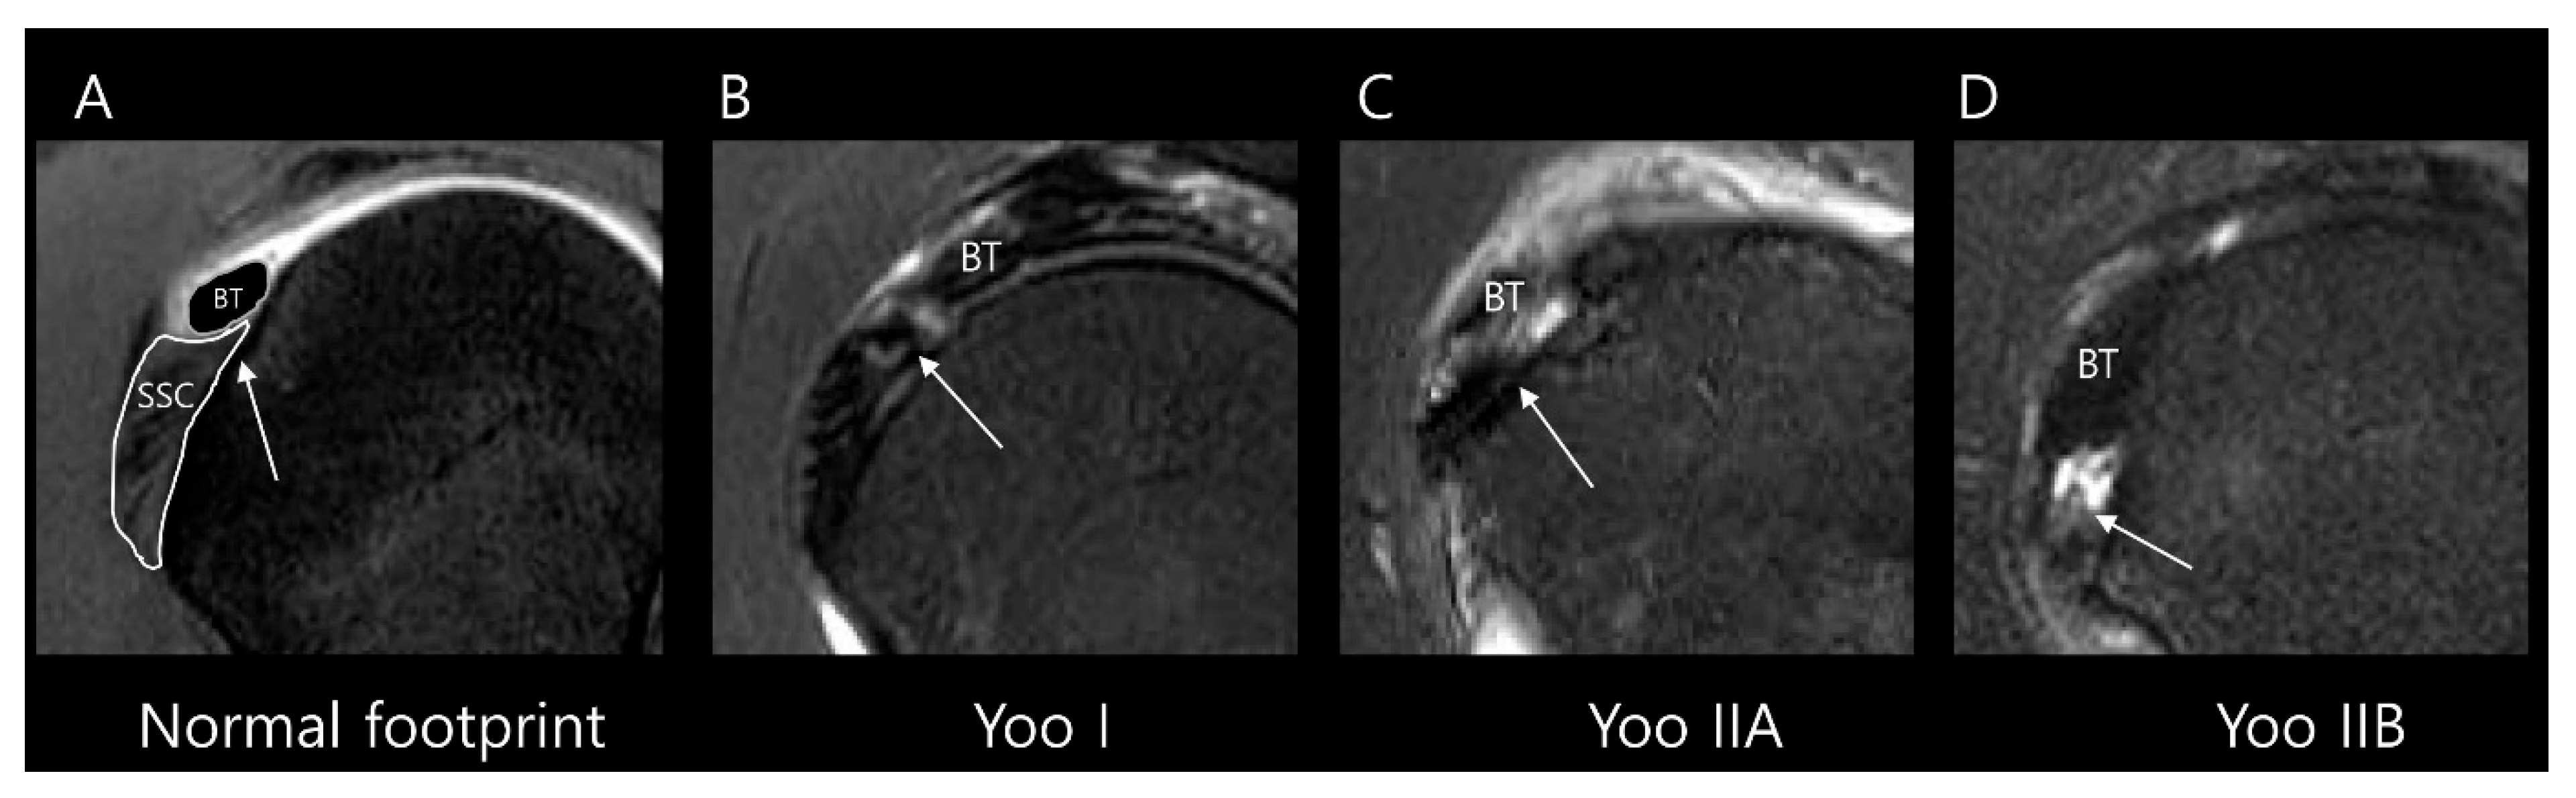

We collected SSC partial thickness tears belonging to Lafosse type 1 on arthroscopy and subclassified them according to the Yoo and Rhee classification (Table 1) using the following parameters (Figure 3) [11]: Yoo type I, leading-edge fraying or longitudinal split; Yoo type IIA, ≤50% detachment of the first facet; Yoo type IIB, >50% detachment of the first facet. It should be noted that, in the Lafosse classification, the surgical indication is defined as a type 2 tear, corresponding to a full thickness tear of the upper one-third. In contrast, the Yoo and Rhee classification defines the surgical indication as Yoo type IIB.

Figure 3.

Subclassification of Lafosse type 1 subscapularis tendon (SSC) partial thickness tears according to the Yoo and Rhee classification. On T2-weighted oblique sagittal images with fat suppression, (A) a normal SSC footprint shows a thin tendinous slip (arrow) in the superior portion, which is closely related to the stability of the biceps tendon (BT). Note that most partial thickness tears (Lafosse type 1) originate from this tendinous slip. (B) Yoo type I tear shows fraying or a longitudinal split at the leading edge (arrow). (C) Yoo type IIA tear is defined as the detachment of less than 50% of the first facet (arrow). (D) Yoo type IIB tear is defined as the detachment of more than 50% of the first facet (arrow).